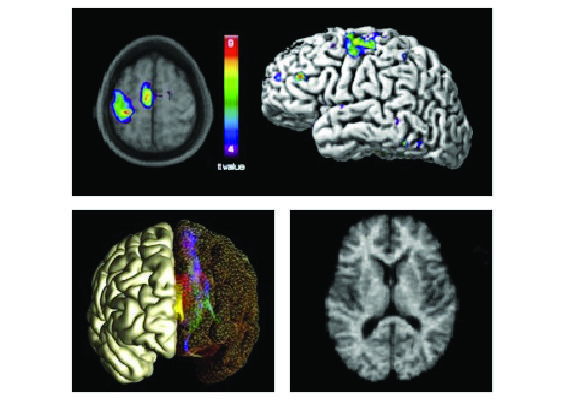

MRI Images

The three images to the right illustrate some of my research activities. On top is a sample functional MRI data set. The bottom right shows white matter fibre tracks of the corpus callosum obtained from diffusion imaging. The lower left image is a map of the location of thalamic lesions created using MR guided high-intensity focused ultrasound to treat patients with essential tremor.